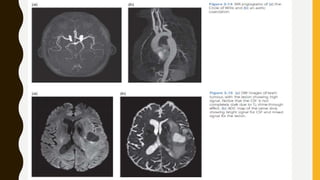

Diffusion-Weighted Images

• Diffusion is a random process by which molecules move gradually within their

environment.

• In MRI we are interested in the diffusion of water molecules, which changes in certain

pathological conditions. For example in tumours which are rapidly proliferating, the

local cell density becomes very high and the extracellular space becomes restricted.

The protons in the extracellular space demonstrate reduced diffusion compared with

normal tissues.

• Diffusion-Weighted Imaging (DWI) is almost always performed using a spin-echo Echo

Planar Imaging (EPI) scan.

• The diffusion sensitivity comes from a pair of very strong gradient pulses, one on

either side of the refocusing RF pulse.

• These gradients have a large amplitude and duration, which means that they force the

TE to be rather long, e.g. 80 ms. This means the DW images are also rather T2-

weighted, a phenomenon known as ‘T2-shine-through’.

• We can separate the T2w effect from the diffusion effect by acquiring a non-DW image

as well as the DWI, and then combining these two images mathematically. The result

is known as the ADC (Apparent Diffusion Coefficient) map.

• Bulk fluids like CSF are dark on DW images, while normal brain tissue has an

intermediate signal level.

• Restricted diffusion, such as we see in stroke or tumours, shows up as high signal

intensity on DWI .

• On the ADC images, the opposite is true: CSF shows up as very high signal (high

diffusion) while restricted diffusion is dark .